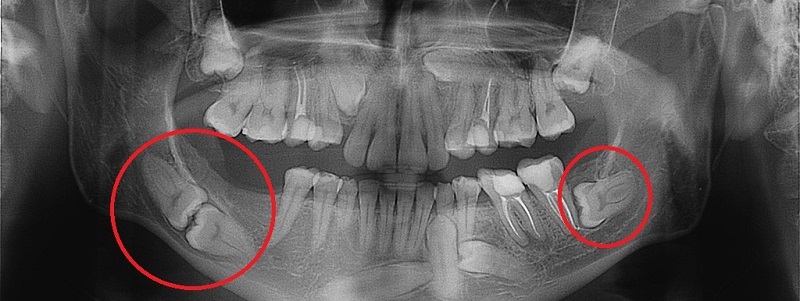

How can I tell if my wisdom tooth is impacted?

Is an X-ray necessary before wisdom tooth extraction?